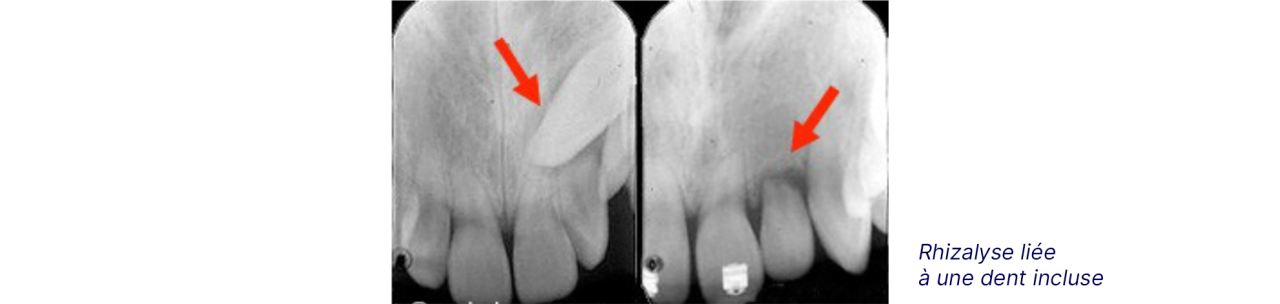

La résorption radiculaire / Rhizalyse

Les racines de certaines dents peuvent raccourcir ou « s’user » durant un traitement d’orthodontie. C’est ce que nous appelons la résorption des racines, résorption radiculaire ou rhizalyse.

Une dent incluse en contact avec la racine d’une dent voisine, des déplacements dentaires trop rapides, une force appliquée trop importante, la succion du pouce associée à un traitement d’orthodontie peuvent être à l’origine d’une résorption radiculaire.

Ce phénomène est irréversible ; une racine plus courte ne « repoussera » pas. Une résorption très importante peut, dans les cas extrêmes et rare, causer la perte d’une dent.

Radiographie exposant le risque de rhizalyse. Radiographie qui montre le risque de rhizalyse.